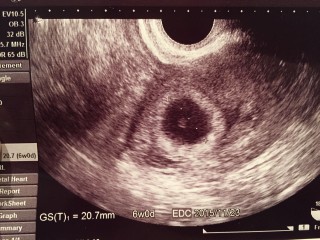

稽留流産を経験しているので、今回は週数ぴったりの大きさで心拍も見えてとても嬉しかったです(*^^*) 先生からも母子手帳をもらってくるように言われました。 CRL:7.3㎜。 GS:23.7㎜